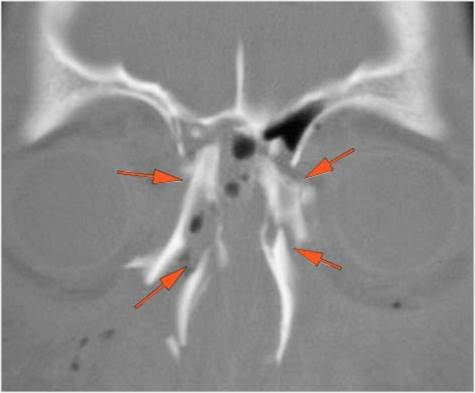

The mesial naso-orbito-ethmoid complex is fractured. Specifically, there is bony injury of the nasal bones or the frontal process of the maxilla and the medial walls of the orbit are abnormal. [Yes/No]

There is injury of the ethmoid complex. Specifically, the ethmoid roof, olfactory fossa and the cribriform plate are fractured and/or significantly dehiscent. [Yes/No]